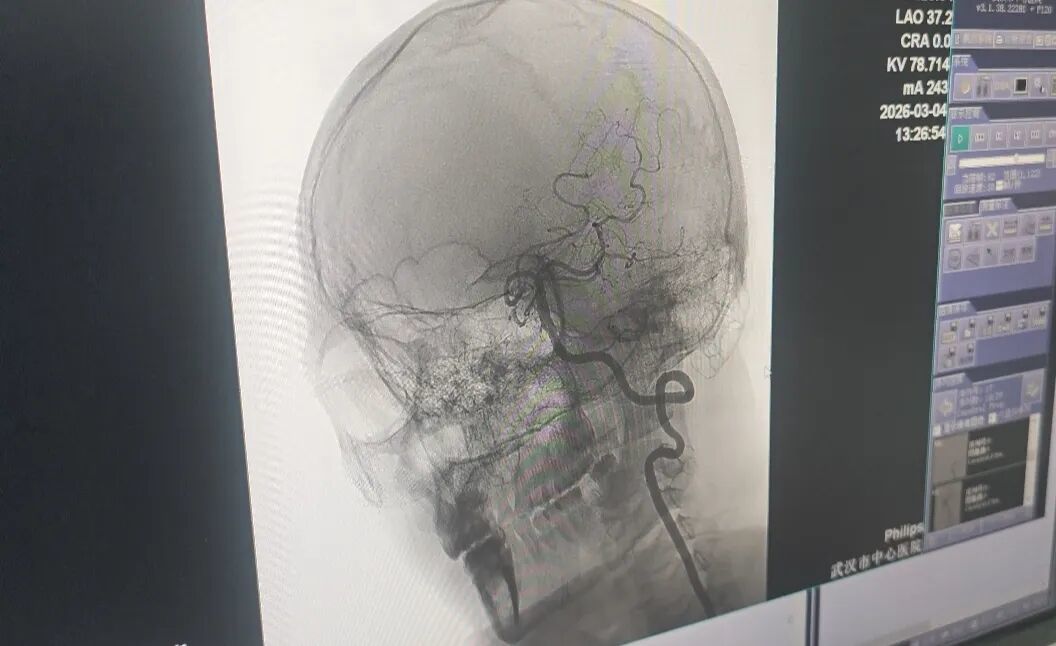

医生精准打通王先生堵塞的血管。

抢救团队考虑到患者椎动脉血管未完全闭塞,于是采用介入下动脉溶栓的方式,精准打通了堵塞的血管。